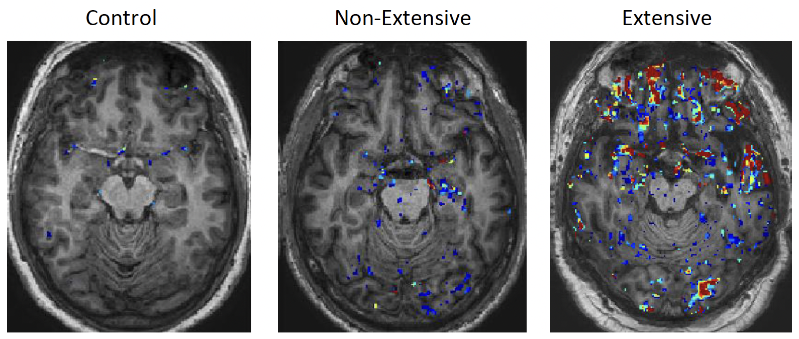

A comparison of the MRI brain scans of people in different cohorts. Left: Control (normal MRI brain scan); Middle: Non-extensive (red/blue pixels showing non-extensive leakage of the BBB); Right: Extensive (red pixelation showing extensive BBB leakage in a retired symptomatic individual). Image: Prof. Matthew Campbell et al. Trinity College Dublin.

“Even years after retirement, retired athletes showed significant BBB disruption compared to age-matched controls,” said Prof. Matthew Campbell, Professor of Neurovascular Genetics and Head of Trinity’s Genetics Department, who led the work with Prof. Colin Doherty, Professor of Epileptology and Head of Trinity’s School of Medicine.

“This suggests that the damage from head impacts is a chronic, ongoing process.”

“We found that retired athletes with the most extensive ‘leakage’ in their brain barrier also scored significantly lower on cognitive tests, specifically those measuring memory and executive function.”